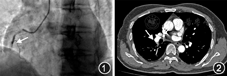

病例1 患者男,63岁,因"胸痛2 h",于2018年1月19日入院。既往无特殊病史。入院体格检查:血压143/70 mmHg(1 mmHg=0.133 kPa),呼吸24次/min,神志清楚;口唇无紫绀,颈静脉无怒张;肺部未闻及啰音;心率60次/min,心律整齐,各瓣膜听诊区未闻及杂音;腹部平软;下肢无水肿。心电图示下壁急性ST段抬高型心肌梗死。心肌肌钙蛋白I 12.000 μg/L,D-二聚体0.32 mg/L,纤维蛋白原3.26 g/L,N末端B型利钠肽原<70 ng/L。冠状动脉造影示:左前降支近段狭窄90%,血流分级为心肌梗死溶栓试验(thrombolysis in myocardial infarction,TIMI)3级;右冠状动脉第一转折处完全闭塞,血流分级为TIMI 0级(图1)。在右冠状动脉闭塞处行血栓抽吸,并置入药物洗脱支架1枚。术前予负荷剂量抗血小板治疗(替格瑞洛180 mg、阿司匹林300 mg),术中静脉推注普通肝素6 000 U,血栓抽吸过程中冠状动脉内先后分次推入替罗非班25 ml,术后常规冠心病二级预防(阿司匹林100 mg,氯吡格雷75 mg,阿托伐他汀20 mg,均每天1次)。患者入院当天大便常规潜血试验(+),考虑合并消化道出血,未使用低分子量肝素。术后患者胸痛症状缓解。次日超声心动图检查示各腔室内径及室壁运动基本正常,左心室射血分数为59%。术后第5天患者突感气短、乏力。心肌肌钙蛋白I为0.310 μg/L,D-二聚体为4.57 mg/L,纤维蛋白原为4.59 g/L。复查心电图未见明显动态变化。下肢血管彩超示双下肢动脉粥样硬化和多发斑块形成,左侧大隐静脉曲张。肺动脉CT血管成像检查示肺动脉主干直径为24 mm,右下肺动脉部分分支充盈缺损(图2),右心径线基本正常,考虑急性肺栓塞。立即皮下注射低分子量肝素4 000 U,每天2次。次日复查凝血功能示D-二聚体为2.86mg/L,纤维蛋白原为3.72 g/L。连续抗凝治疗7 d后,患者症状好转,复查D-二聚体为0.75 mg/L,纤维蛋白原为3.98 g/L,予出院。出院3个月后,复查肺动脉CT血管成像检查示血栓完全消散。

病例2患者男,72岁,因"突发胸痛6 h",于2016年12月29日入院。既往有持续性心房颤动和消化道出血病史。入院体格检查:血压120/80 mmHg,呼吸22次/min,神志清楚;口唇无紫绀,颈静脉无怒张;双侧肺底可闻及少许湿性啰音;心率70次/min,心律绝对不齐,心音强弱不等,各瓣膜听诊区未闻及杂音;腹部平软;下肢无水肿。心电图示下壁和正后壁急性ST段抬高型心肌梗死,心房颤动。心肌肌钙蛋白I为22.000 μg/L,D-二聚体为0.68 mg/L,纤维蛋白原为2.78 g/L,N末端B型利钠肽原为1 880 ng/L。冠状动脉造影检查示左回旋支远端自第二钝缘支发出后完全闭塞,血流分级为TIMI 0级(图3)。行血栓抽吸后,置入药物洗脱支架1枚。术前予负荷剂量双联抗血小板药物治疗(氯吡格雷600 mg、阿司匹林300 mg),造影前静脉推注普通肝素5 000 U,术中经血栓抽吸导管冠状动脉内推注替罗非班20 ml,术后常规冠心病二级预防(氯吡格雷75 mg、瑞托伐他汀20 mg,均每天1次)。患者入院当日大便常规潜血试验(+),考虑合并消化道出血,未使用阿司匹林和低分子量肝素。嘱患者卧床休息,适当床上活动,术后当天患者胸痛缓解。次日超声心动图示左心室射血分数为42%,左心房扩大(内径46 mm),下壁运动幅度减低,二尖瓣、三尖瓣和主动脉瓣均为中度反流。术后第4天复查心肌肌钙蛋白I为0.63 μg/L,D-二聚体为1.09 mg/L,纤维蛋白原为4.13 g/L,N末端B型利钠肽原为4 810 ng/L。术后第10天,患者病情稳定出院。出院后第2天,患者活动时出现气短,伴咯血,再次住院。复查心肌肌钙蛋白I为0.097 μg/L,D-二聚体最高为11.28 mg/L,纤维蛋白原最高为4.72 g/L,N末端B型利钠肽原最高为9 910 ng/L,炎症标志物(降钙素原和超敏C反应蛋白)轻度升高,大便常规潜血试验(++++)。床旁超声心动图检查示三尖瓣和二尖瓣中度反流,重度肺动脉高压(78 mmHg),左心扩大(左心房内径44 mm,左心室内径55 mm),左心室下壁和侧壁运动幅度减低,左心室射血分数为45%。患者诊断为下壁和后壁急性心肌梗死、慢性心力衰竭、心房颤动、社区获得性肺炎和消化道出血,予抗感染、抗心力衰竭、抑酸和护胃等治疗,并嘱患者卧床休息,暂禁食。治疗20 d后效果不理想,遂行上下肢血管彩超检查,示双侧股静脉血流瘀缓,管腔内可见云雾状自发显影,双侧肱静脉和左侧头静脉血流瘀缓。肺动脉CT血管成像检查示左肺动脉主干、多分支和右肺动脉多分支可见充盈缺损(图4),慢性支气管炎并肺部感染,右肺实变。患者诊断为急性肺栓塞,立即皮下注射低分子量肝素4 000 U,每天2次;华法林3 mg,每天1次。患者抗凝治疗后第3天复查D-二聚体为4.45mg/L,纤维蛋白原为3.13 g/L,国际标准化比值(international normalized ratio,INR)为6.77,遂停用低分子量肝素,调整华法林剂量。患者逐渐好转,并在病情稳定后出院。患者出院后继续口服华法林抗凝。出院后第10天患者D-二聚体为1.42 mg/L,纤维蛋白原为3.72 g/L,INR为1.82。同时,肺动脉CT血管成像示原左肺动脉主干及分支内血栓较前明显缩小,部分消失,右肺动脉及分支内未见明显充盈缺损。